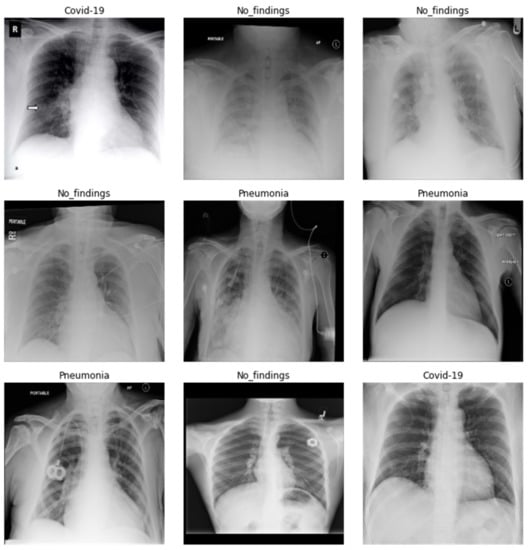

The results of the DenseNet201 and SqueezeNet1_0 models after fine-tuning are showcased in Figure 17 and Figure 18. In Figure 17 and Figure 18, the first represents the ground truth value, and the second represents the predicted value for the given image below.

Figure 17. Results of DenseNet201 model after fine-tuning.

Figure 18. Results of SqueezeNet1_0 model after fine-tuning.